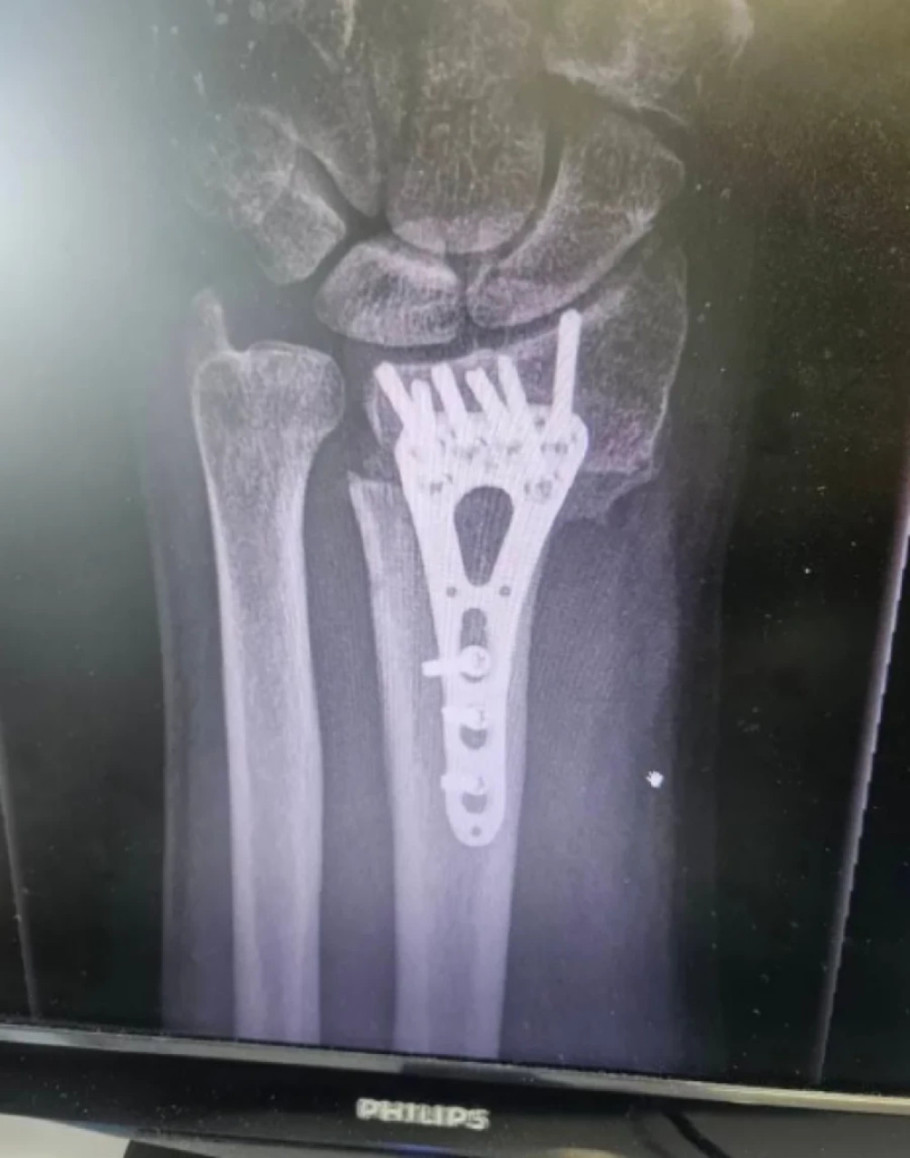

Stanković je objavio uznemirujuću fotografiju iskrivljene ruke iz bolnice zbog koje je morao da se podvrgne operaciji. Sve to je pratila emotivna poruku u kojoj je otkrio da je sve sada u redu i da se uspešno oporavlja.

- Ovako je to izgledalo pre tri meseca, a danas je sve u redu. Slomio sam ruku i operisali su me u Opštoj bolnici Sisak na čelu s doktorkom Abelom Balaškom. Ruka je zacelila i hvala im što su svoj posao odradili profesionalno i s ljubavlju - napisao je Stanković.